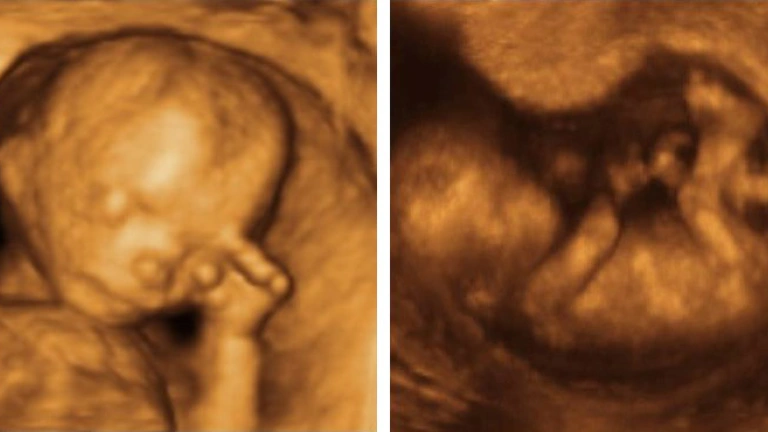

Un estudio realizado por la Universidad de Durham, en el Reino Unido, ha revelado que los bebés que se encuentran en el vientre materno son capaces de reaccionar a lo que comen sus madres. La doctora Beyza Ustun esplica que para descubrirlo dieron a las madres embarazadas cápsulas de sabores 20 minutos antes de hacerle una ecografía.

El estudio es el primero que demuestra reacciones del feto a distintos sabores. En total, participaron 100 embarazadas de entre 32 y 36 semanas de gestación . Primero hicieron una ecografía y luego otra a las seis semanas. “La razón de hacer dos ecografías era ver las expresiones faciales y cómo cambian después de 6 semanas, porque son más complejas cuando se forman los músculos, son expresiones más maduras”, explica la investigadora.

La reacción del bebé en el útero tras comer col rizada

Como la propia doctora Ustun explica, “si estaban expuestas al sabor de la zanahoria, ponían una cara similar a la sonrisa, mientras que con la col rizada tenían cara de tristeza”. Un hallazgo que el divulgador científico y colaborador de La Linterna, Jorge Alcalde, calificaba con Ángel Expósito de “sorprendente”. “Lo primero que sorprende es que en pleno proceso de gestación ya se estén produciendo las primeras reacciones al gusto, y dependen mucho del olfato”.